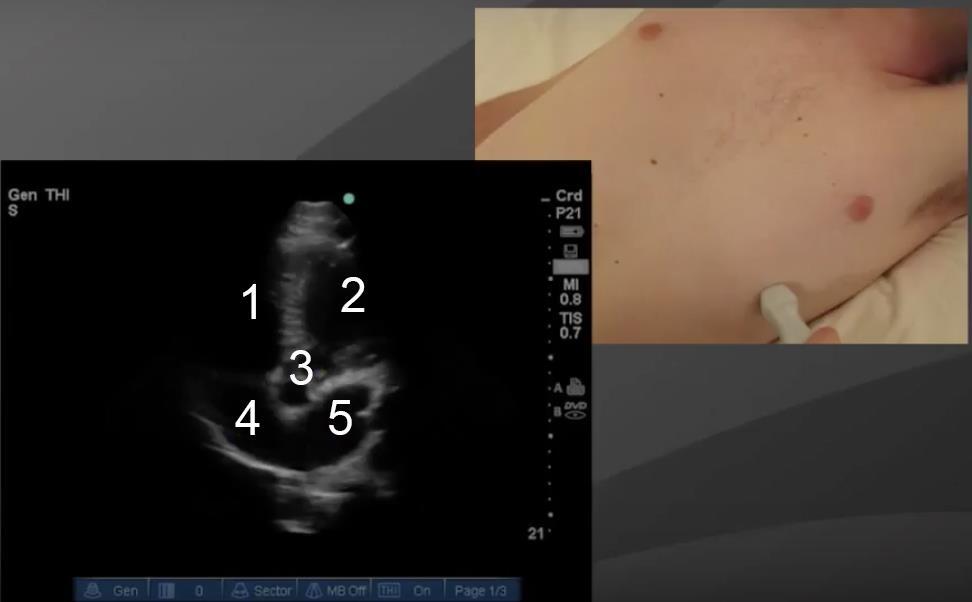

Cardíaco: Vista apical de 5 cámaras - Imagen

1. Ventrículo derecho (VD)

2. Ventrículo izquierdo (VI)

3. Aorta (AO)

4. Aurícula derecha (AD)

5. Aurícula izquierda (AI)